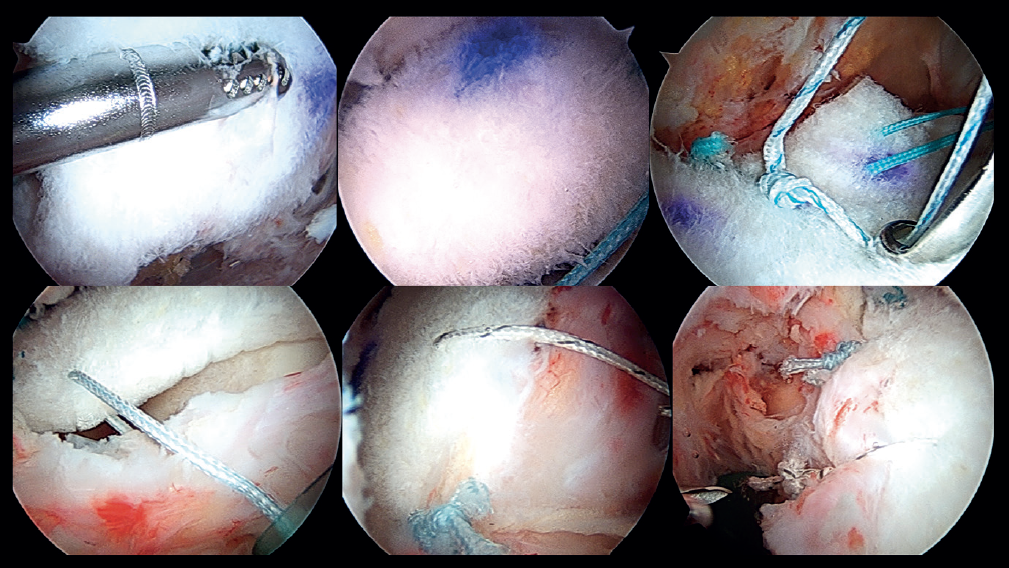

Preparation of the segmental acetabular reconstruction

For the treatment of the labrum we perform labral reconstruction with tibialis anterior allograft using the pull through technique(7) and tensionable technology, employing the posterolateral portal as accessory portal for positioning the graft. For this procedure, use is made of a tibialis anterior allograft that is prepared to obtain a diameter of 6-7 mm and a length of about 18 cm. Using FiberLoop® suture, the extremities are prepared with the SpeedWhip® (Arthrex) technique (Figure 5). Once the graft has been prepared, four 1.8 mm FiberTak® Knotless anchorings with tensionable technology (Arthrex) are implanted in the acetabular margin in the 11 to 3 o'clock position, distal to the previously mentioned anchorings, which we will refer to as second row anchorings, through the middle anterior portal or from the DALA, and then we retrieve the sutures of these anchorings through the DALA. During perforation and pre-drilling of the anchoring, the arthroscope is to be placed in a position allowing assessment of the joint cartilage, in order to make sure that the drill is not located between the subchondral bone and the surface of the joint cartilage. In order to prevent the anchorings from penetrating into the acetabular cartilage, the angle of the margin must be determined to ensure adequate placement. The successive filaments are placed in the field aligned and spread out in a fan-like manner from inferior-anterior to posterior-superior.

Introduction of the graft for labral reconstruction

Once all the sutures have been positioned, forceps are introduced from the posterolateral portal, taking care that they lie posterior to the last anchoring, with positioning within the joint. From the middle anterior portal we introduce the suture anchored to what will be the posterior part of the graft, likewise taking care that it lies anterior to the most anterior anchoring. This suture is retrieved from the posterolateral portal using the previously introduced forceps, applying traction to introduce the graft, and making it emerge through the posterolateral portal (Figure 6). At this point we fix the graft by passing sutures from the most anterior anchoring of the second row of anchorings, through the anterior part of the tibialis tendon, and it is then finally introduced and sutured. The sutures are then passed around the tendon graft in sequence, and are tightened little by little, maintaining traction from the posterolateral portal, and fixing and positioning the entire plasty from anterior to posterior (Figure 7). Once all these steps have been completed, the excess graft is radiofrequency amputated from the posterolateral portal.